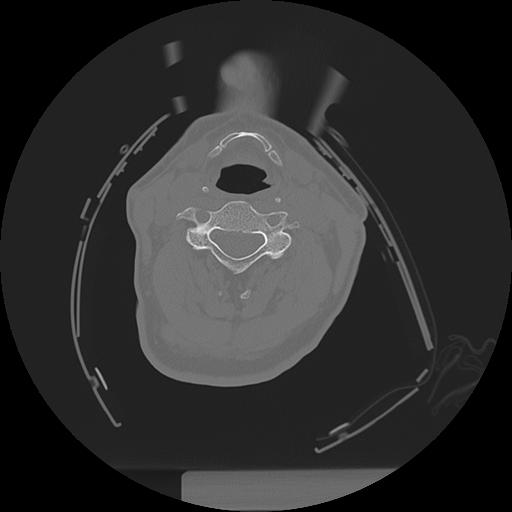

11 HUESO,,Axial,2.0,HUESO,,